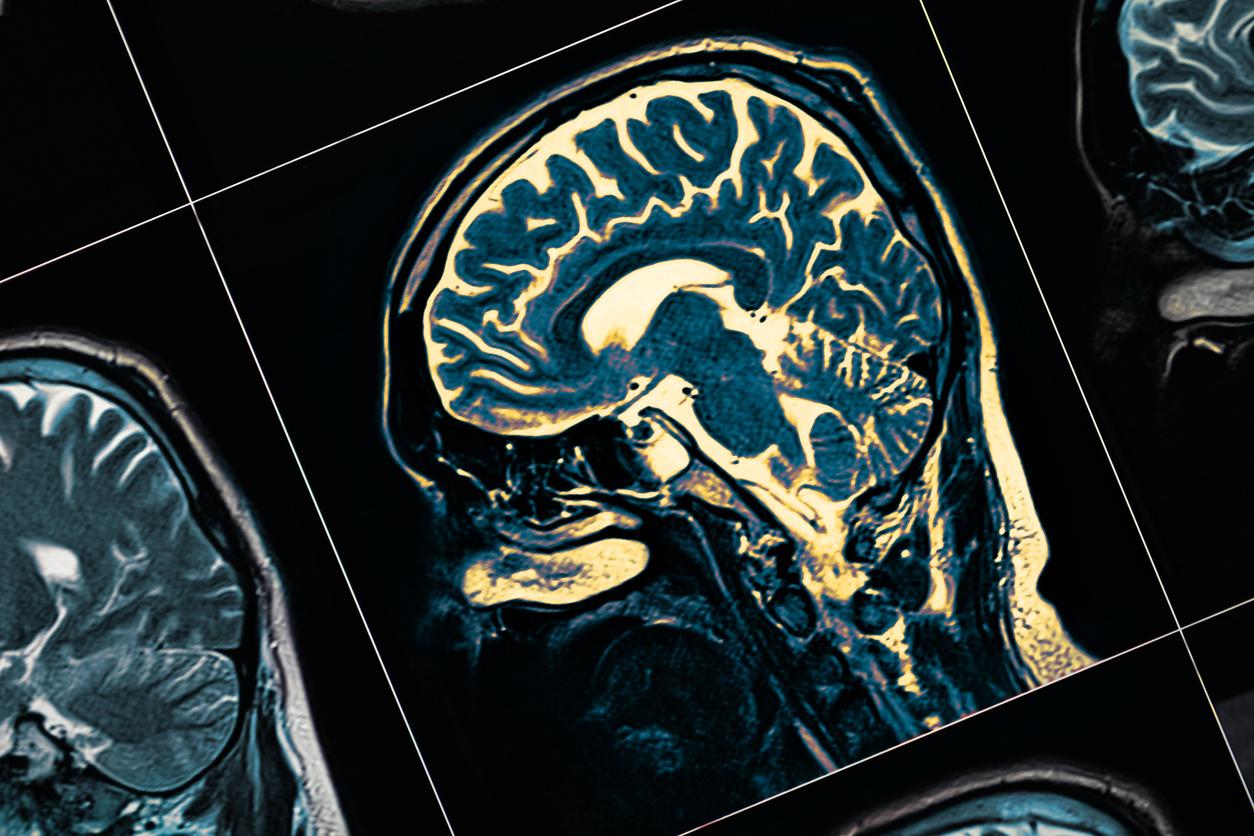

J’ai été neuro-stimulée en 2014, avec des électrodes dans la tête, ce qui a bien arrangé mes dysquinésies (mouvements involontaires des membres et du tronc) et mes troubles du sommeil. Cela m’a aussi permis de baisser le dosage mes traitements de fonds, car j’étais au maximum de ce qu’on pouvait me donner à l’époque.